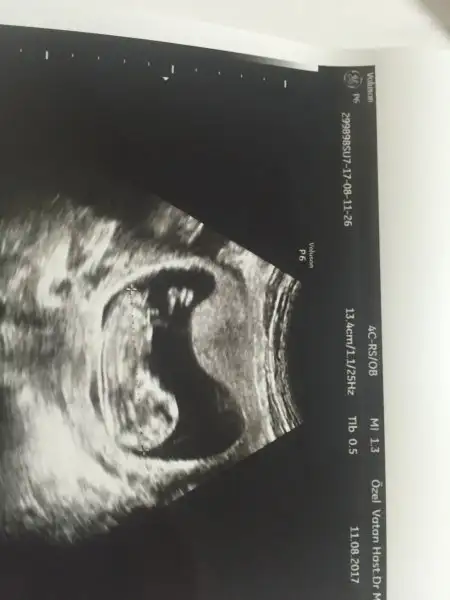

Kızlar 0,97 çıktı ense kalınlığı çok şükür

Son adet tarihimi de 23 mayıstan 14 mayısa çekti çünkü 12+5 çıktı yavrucinsiyete de bir şey söyledi ama bi bakın bakalım :)